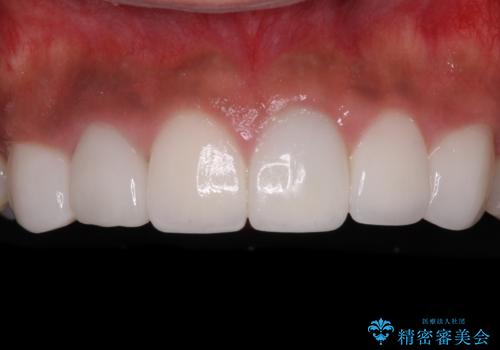

矮小歯のセラミック治療 小さい前歯を自然に仕上げる

- 前歯の矮小歯に貼り付けられていたラミネートベニアが外れてしまったとのことで来院された患者様です。

反対側の矮小歯は裏打ちが金属であったため、両方の歯ともにオールセラミッククラウンにて補綴することとしました。

前歯の隙間や、周りの歯と色合いの違いなどはあまり気にしていらっしゃらなかったため、矮小歯の2歯を自然な大きさに仕上げました。

とても自然な歯が装着されたとのことで、患者様には大変満足していただきました。